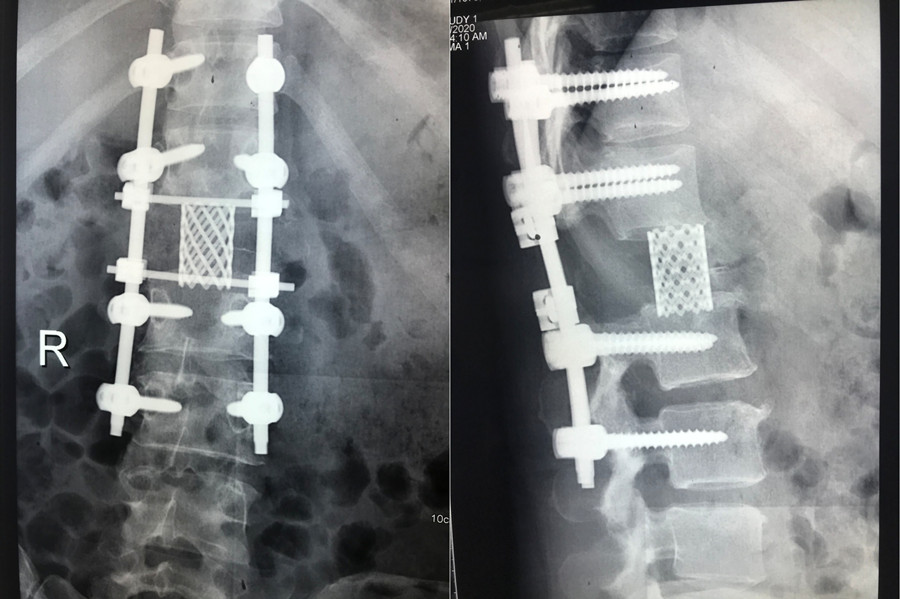

该患者家庭经济拮据,且疫情期间无法外请北京专家前来手术,患者及家属辗转自治区多家医院找到赵岩医生,赵岩团队经过反复讨论和充分准备,最终在麻醉科(手术室)紧密配合下独立完成一期后路固定+En-bloc腰1椎体肿瘤切除术+椎体重建术,该手术首先行后路脊柱固定,其次从后方经椎弓根将病变节段的后部结构整块切除,再向前方分离骨膜和椎体周围血管(这是手术风险最大的步骤),分离彻底后将椎体一并整块切除,最后重建脊柱前中柱。

脊柱截骨手术分六级,此手术属五级截骨手术(VCR),是单椎体最高级截骨手术。术中克服了没有介入科血管栓塞辅助支持等重重困难,最终整个手术仅耗时2个小时顺利将肿瘤椎体完整切除并行腰1椎体重建,出血量500ml。

该手术的成功实施不仅体现了91直播 脊柱外科对En-bloc技术的熟练掌握,更成功填补了自治区内利用En-bloc技术行脊柱肿瘤手术的技术空白,标志91直播 脊柱外科技术达到国内一流水平。

术后